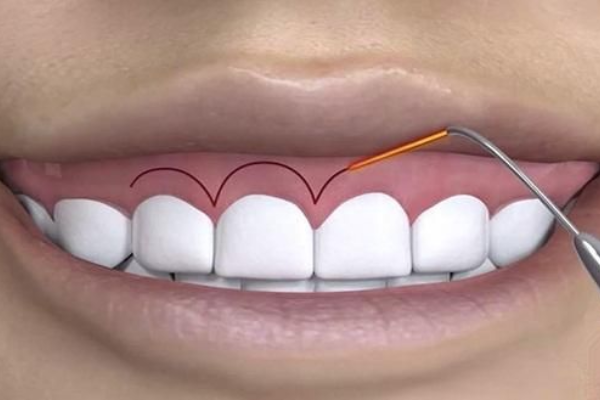

If you feel your gums are too prominent when you smile, our laser gum contouring or surgical procedures can reshape your gumline for a balanced, aesthetically pleasing smile.

We use the latest techniques and laser dentistry for precise, pain-free treatment.